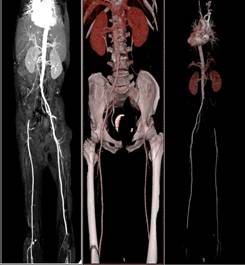

(二)血管造影:明足以察秋毫之末

我院拥有吉安市唯一一台64排128层CT,可进行CT骨三维重建、CT血管造影等。同时拥有DSA血管造影设备(大C臂及中C臂等),为我院开展深静脉造影、内脏血管造影及治疗等奠定了基础。